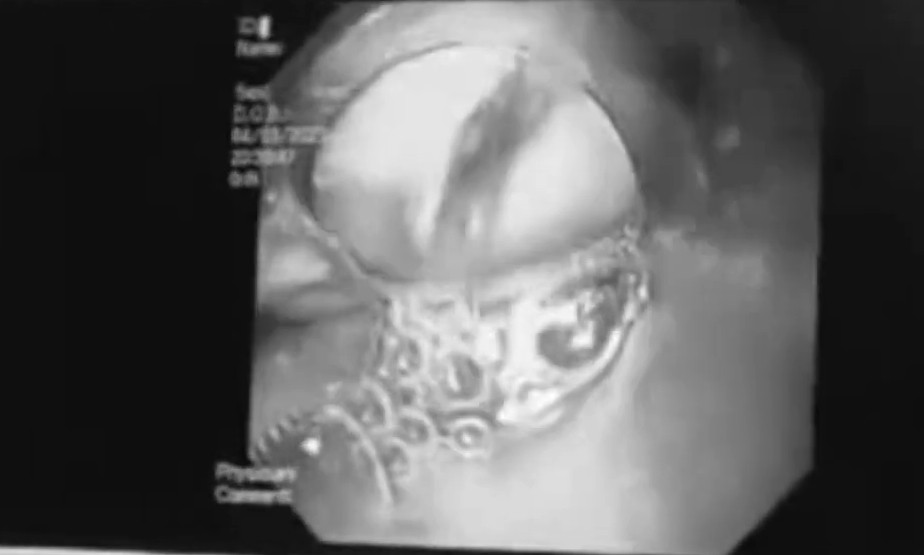

Ngày 8/3, Bệnh viện đa khoa huyện Nghi Lộc, tỉnh Nghệ An vừa cấp cứu cho một phụ nữ trong tình trạng nguy kịch, do nuốt mật lợn để chữa đau bụng.